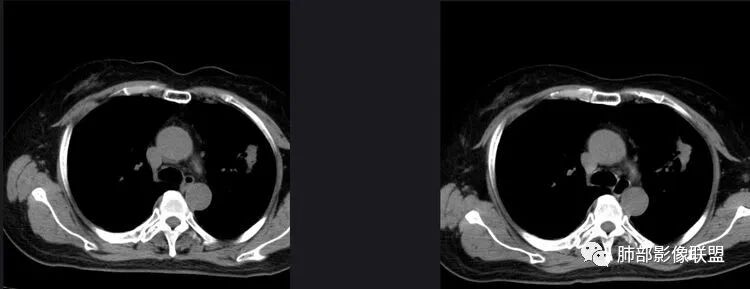

以下是两个时间点左右对比

2019.11.26  👇                           2020.01.20👇                                            2019.11.26片

2020.01.20片